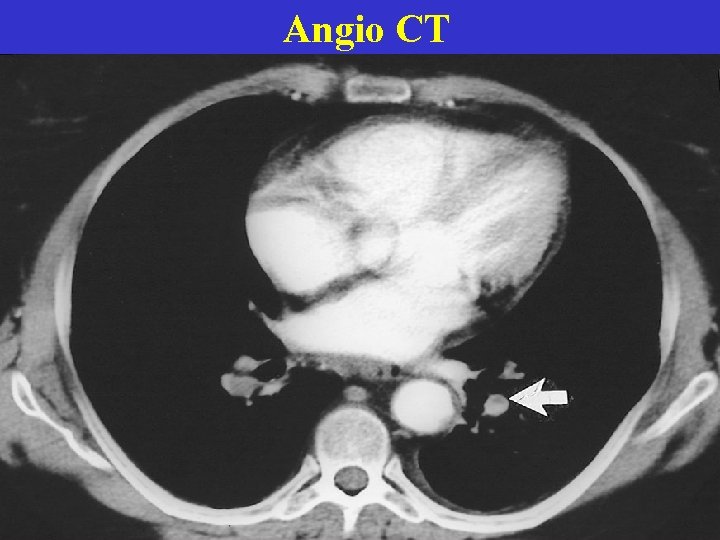

Angio CT